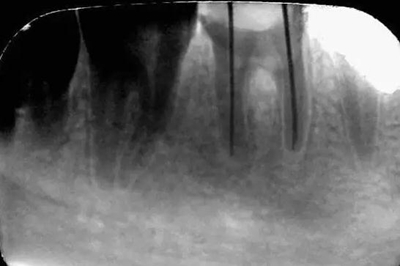

初診時X光片:根分歧炎癥懷疑有底穿,和患者交待病情和費用后開始治療。

初尖銼X光片:現(xiàn)在根測儀的準(zhǔn)確性的卻非常之高。

主尖銼X光片: